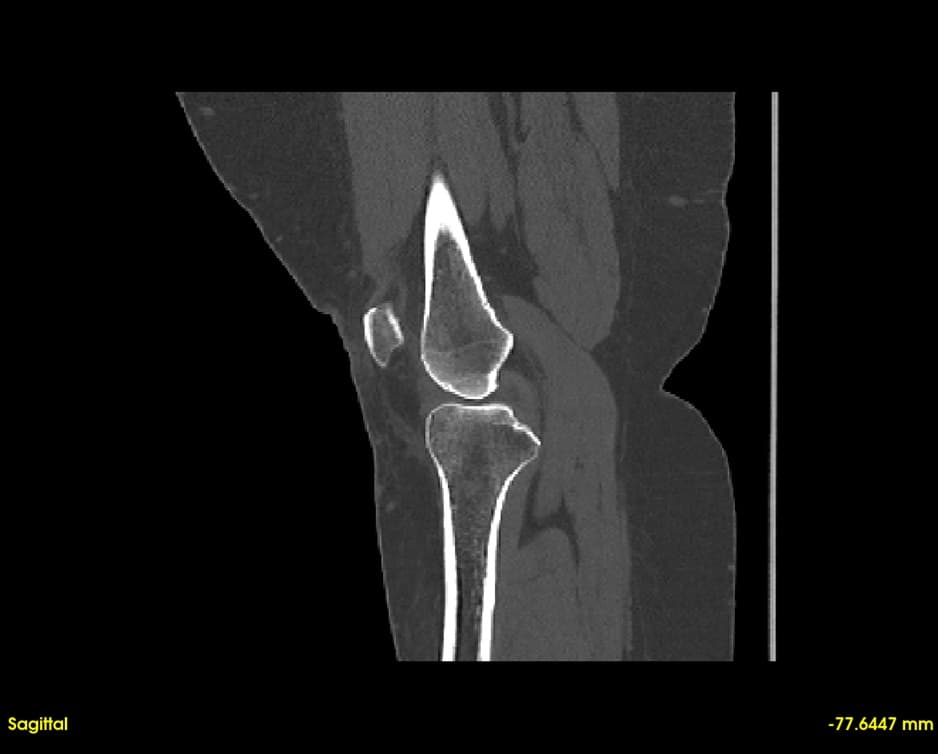

Simultaneous axial, sagittal, and coronal views. Navigate through slices with synchronized cross-referencing.

Explore slices with multi-planar reconstruction views

Segment bones, vasculature, and soft tissues with precision. User-friendly tools for accurate anatomical boundary delineation.